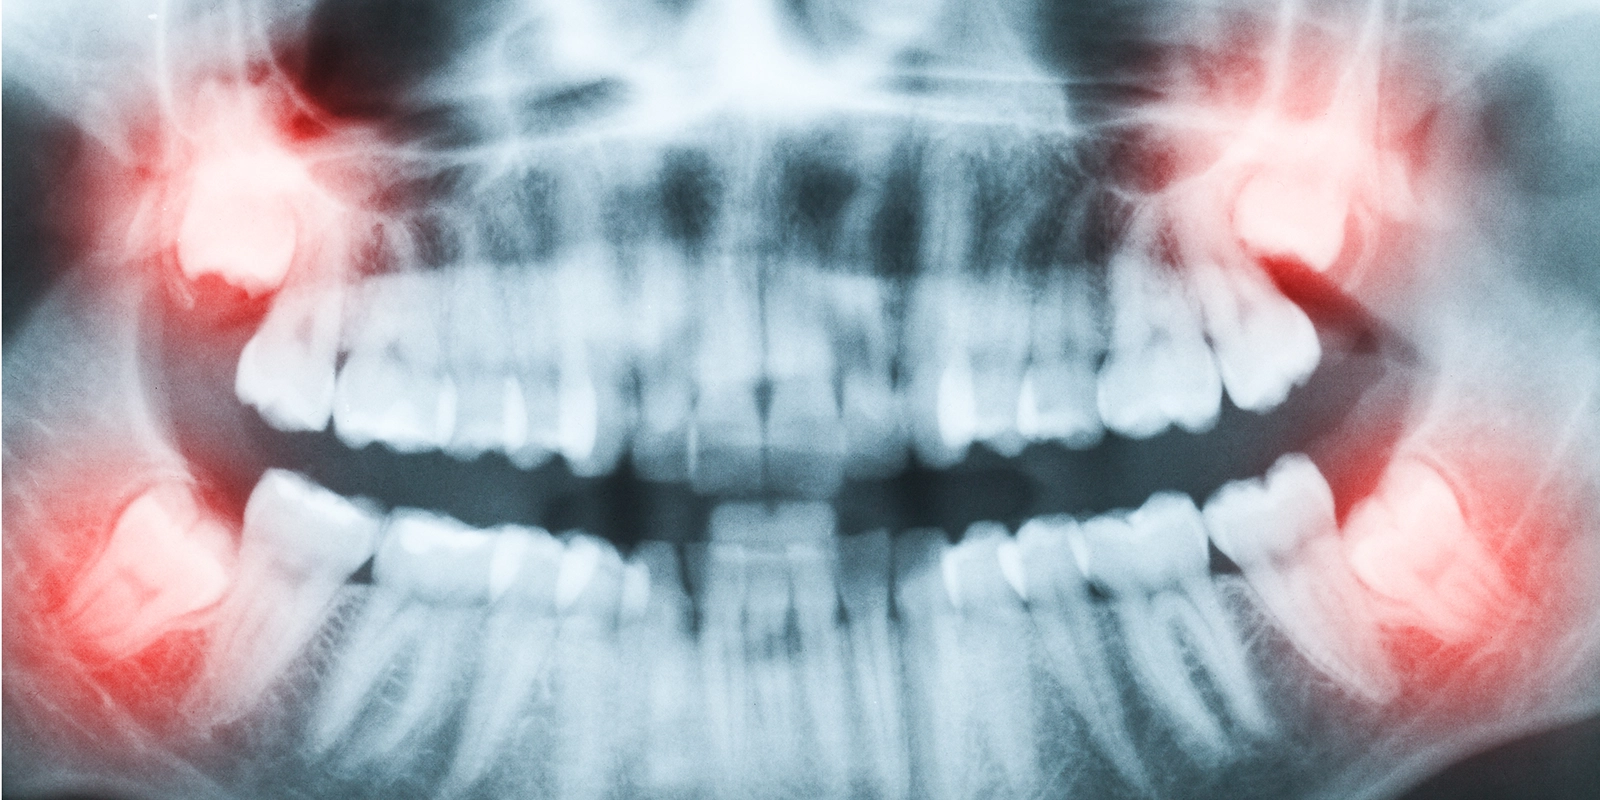

最も一般的な口腔外科治療の一つです。親知らず(第三大臼歯)は、現代人の顎が小さくなったことで、正常に生えてこないケースが増えています。

埋伏智歯と呼ばれる、骨や歯肉の中に埋まったままの親知らずは、周囲の歯に悪影響を与えたり、感染を起こしたりする原因となります。こうした場合、歯肉を切開し、時には骨を削って歯を取り出す必要があります。

- 詳細な診査・診断 レントゲン撮影やCT検査により、患部の詳細な状態を把握します。三次元的な画像診断により、より安全で確実な治療計画を立てることができます。